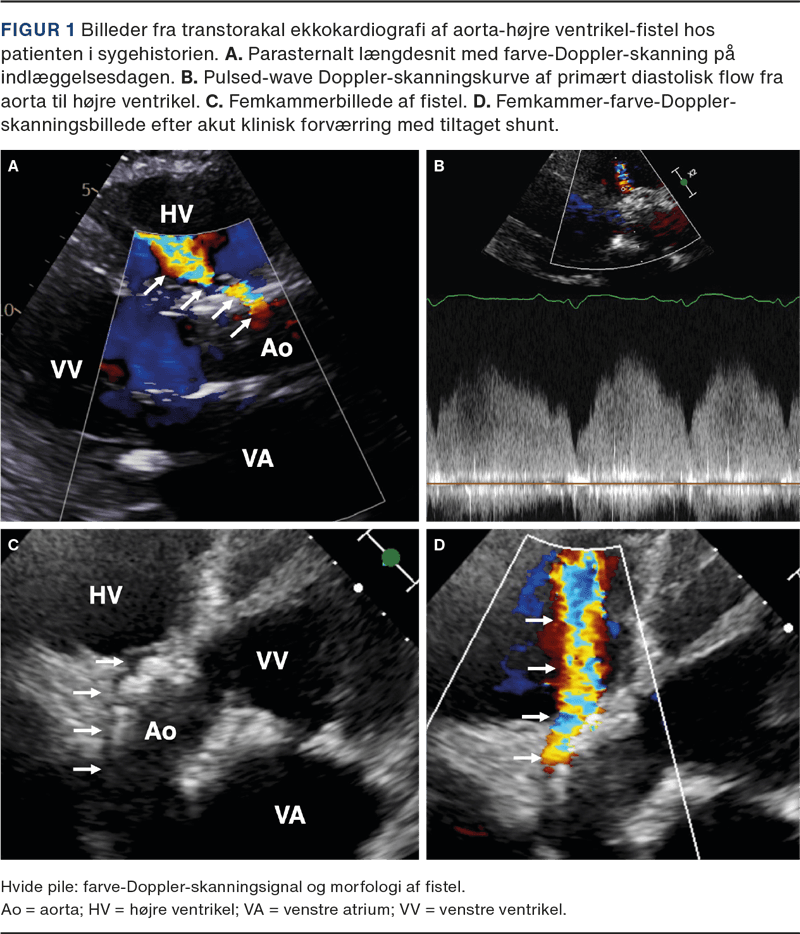

Akut ekkokardiografi påviste fistel fra aortaroden til højre ventrikel og hæmodynamisk betydende shunt (Figur 1 og video). Der var ikke ekkokardiografiske fund tydende på akut lungeemboli. Ved gennemgang af ekkokardiografier i forløbet seks uger tidligere var fistlen allerede til stede et døgn postproceduralt, men mindre udtalt. Trods understøttende behandling descenderede tilstanden hurtigt, og patienten afgik ved døden et døgn efter debut af de akutte smerter.

Akut forværring med svær rygsmerte, forhøjet D-dimerniveau, tiltagende shunt og udvikling af shock kan have været forårsaget af yderligere, akut fistulering og/eller dissektion i aorta ascendens. Blodtrykket var ikke forhøjet i døgnet op til de akutte smerter, og der var ingen oplagt forklaring på, hvorfor den akutte progression først indtraf seks uger postproceduralt. Umiddelbart efter de akutte smerter steg pulstrykket markant, foreneligt med den påviste diastoliske shunt fra aorta til højre ventrikel.